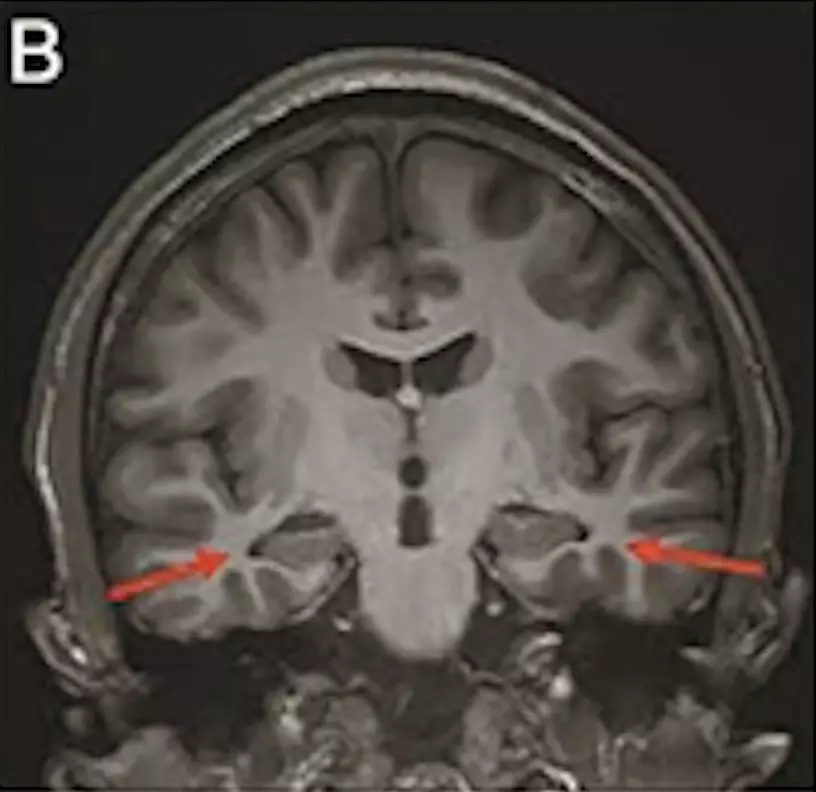

最年輕的19歲阿茲海默症男子腦部掃描結果:

該名19歲男子到醫院接受多項檢查,包括腦脊液指標檢測及正電子掃描。結果顯示,他出現輕度腦萎縮等症狀,最終被臨床診斷為「阿茲海默症」。